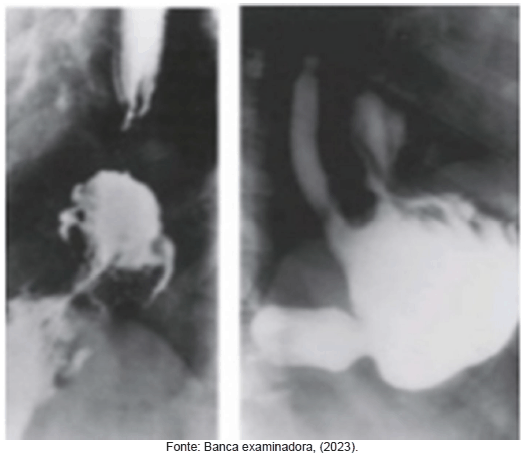

Paciente, sexo masculino, 58 anos, casado, obesidade grau II, natural e procedente de Paraopeba-MG. Paciente procura pronto atendimento relatando que estava em uma churrascaria com amigos quando se abaixou para amarrar os sapatos e sentiu dor importante em região epigástrica e retroesternal. Procurou atendimento médico, tendo sido solicitado o exame exposto na figura abaixo.

Em relação ao caso, informe verdadeiro (V) ou falso (F) as assertivas abaixo e, em seguida, marque a opção que apresenta a sequência correta.

( ) O resultado do exame ilustrado na figura acima é suficiente para embasar a indicação cirúrgica.

( ) Lacerações no esôfago à endoscopia podem indicar que o escore de DeMeester seja superior a 14,7.

( ) Uma motilidade esofágica comprometida indica como melhor opção uma fundoplicatura parcial.

( ) A endoscopia não tem indicação nesse caso, porque não acrescenta nenhuma informação para o tratamento desse paciente.